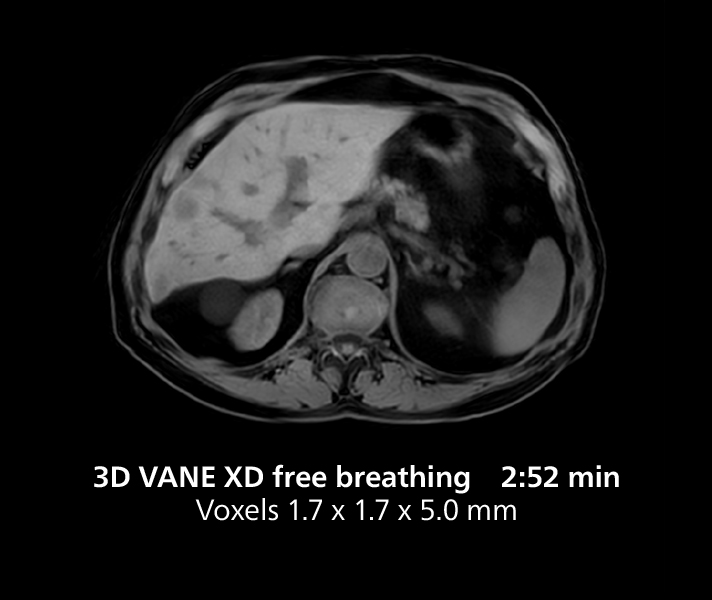

Liver imaging using MR 5300

This case includes 3D free breathing and 4D dynamic free breathing MRI of a metastasized liver. A high quality fatsat sequence with good resolution is obtained in 1:36 minutes with T2-weighted MultiVane XD.

Liver imaging using MR 5300

This case includes 3D free breathing and 4D dynamic free breathing MRI of a metastasized liver. A high quality fatsat sequence with good resolution is obtained in 1:36 minutes with T2-weighted MultiVane XD.